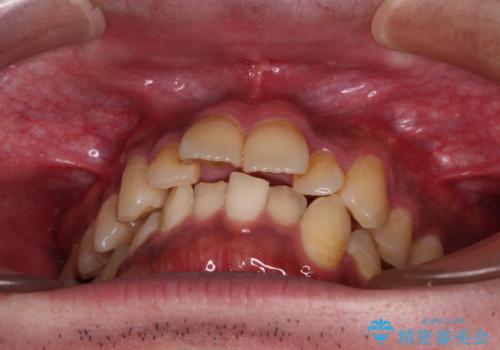

- 主張してる上の前歯を気にして来院された患者様です。

上の前歯が出ているものの、口元が出っ歯というわけではなかったため、非抜歯矯正にて治療を行うこととしました。

下顎に対して上顎歯列が全体的に前方に位置しており、特に右側の奥歯の咬み合わせの前後のズレが大きいため、補助装置を用いて咬み合わせを改善することとしました。